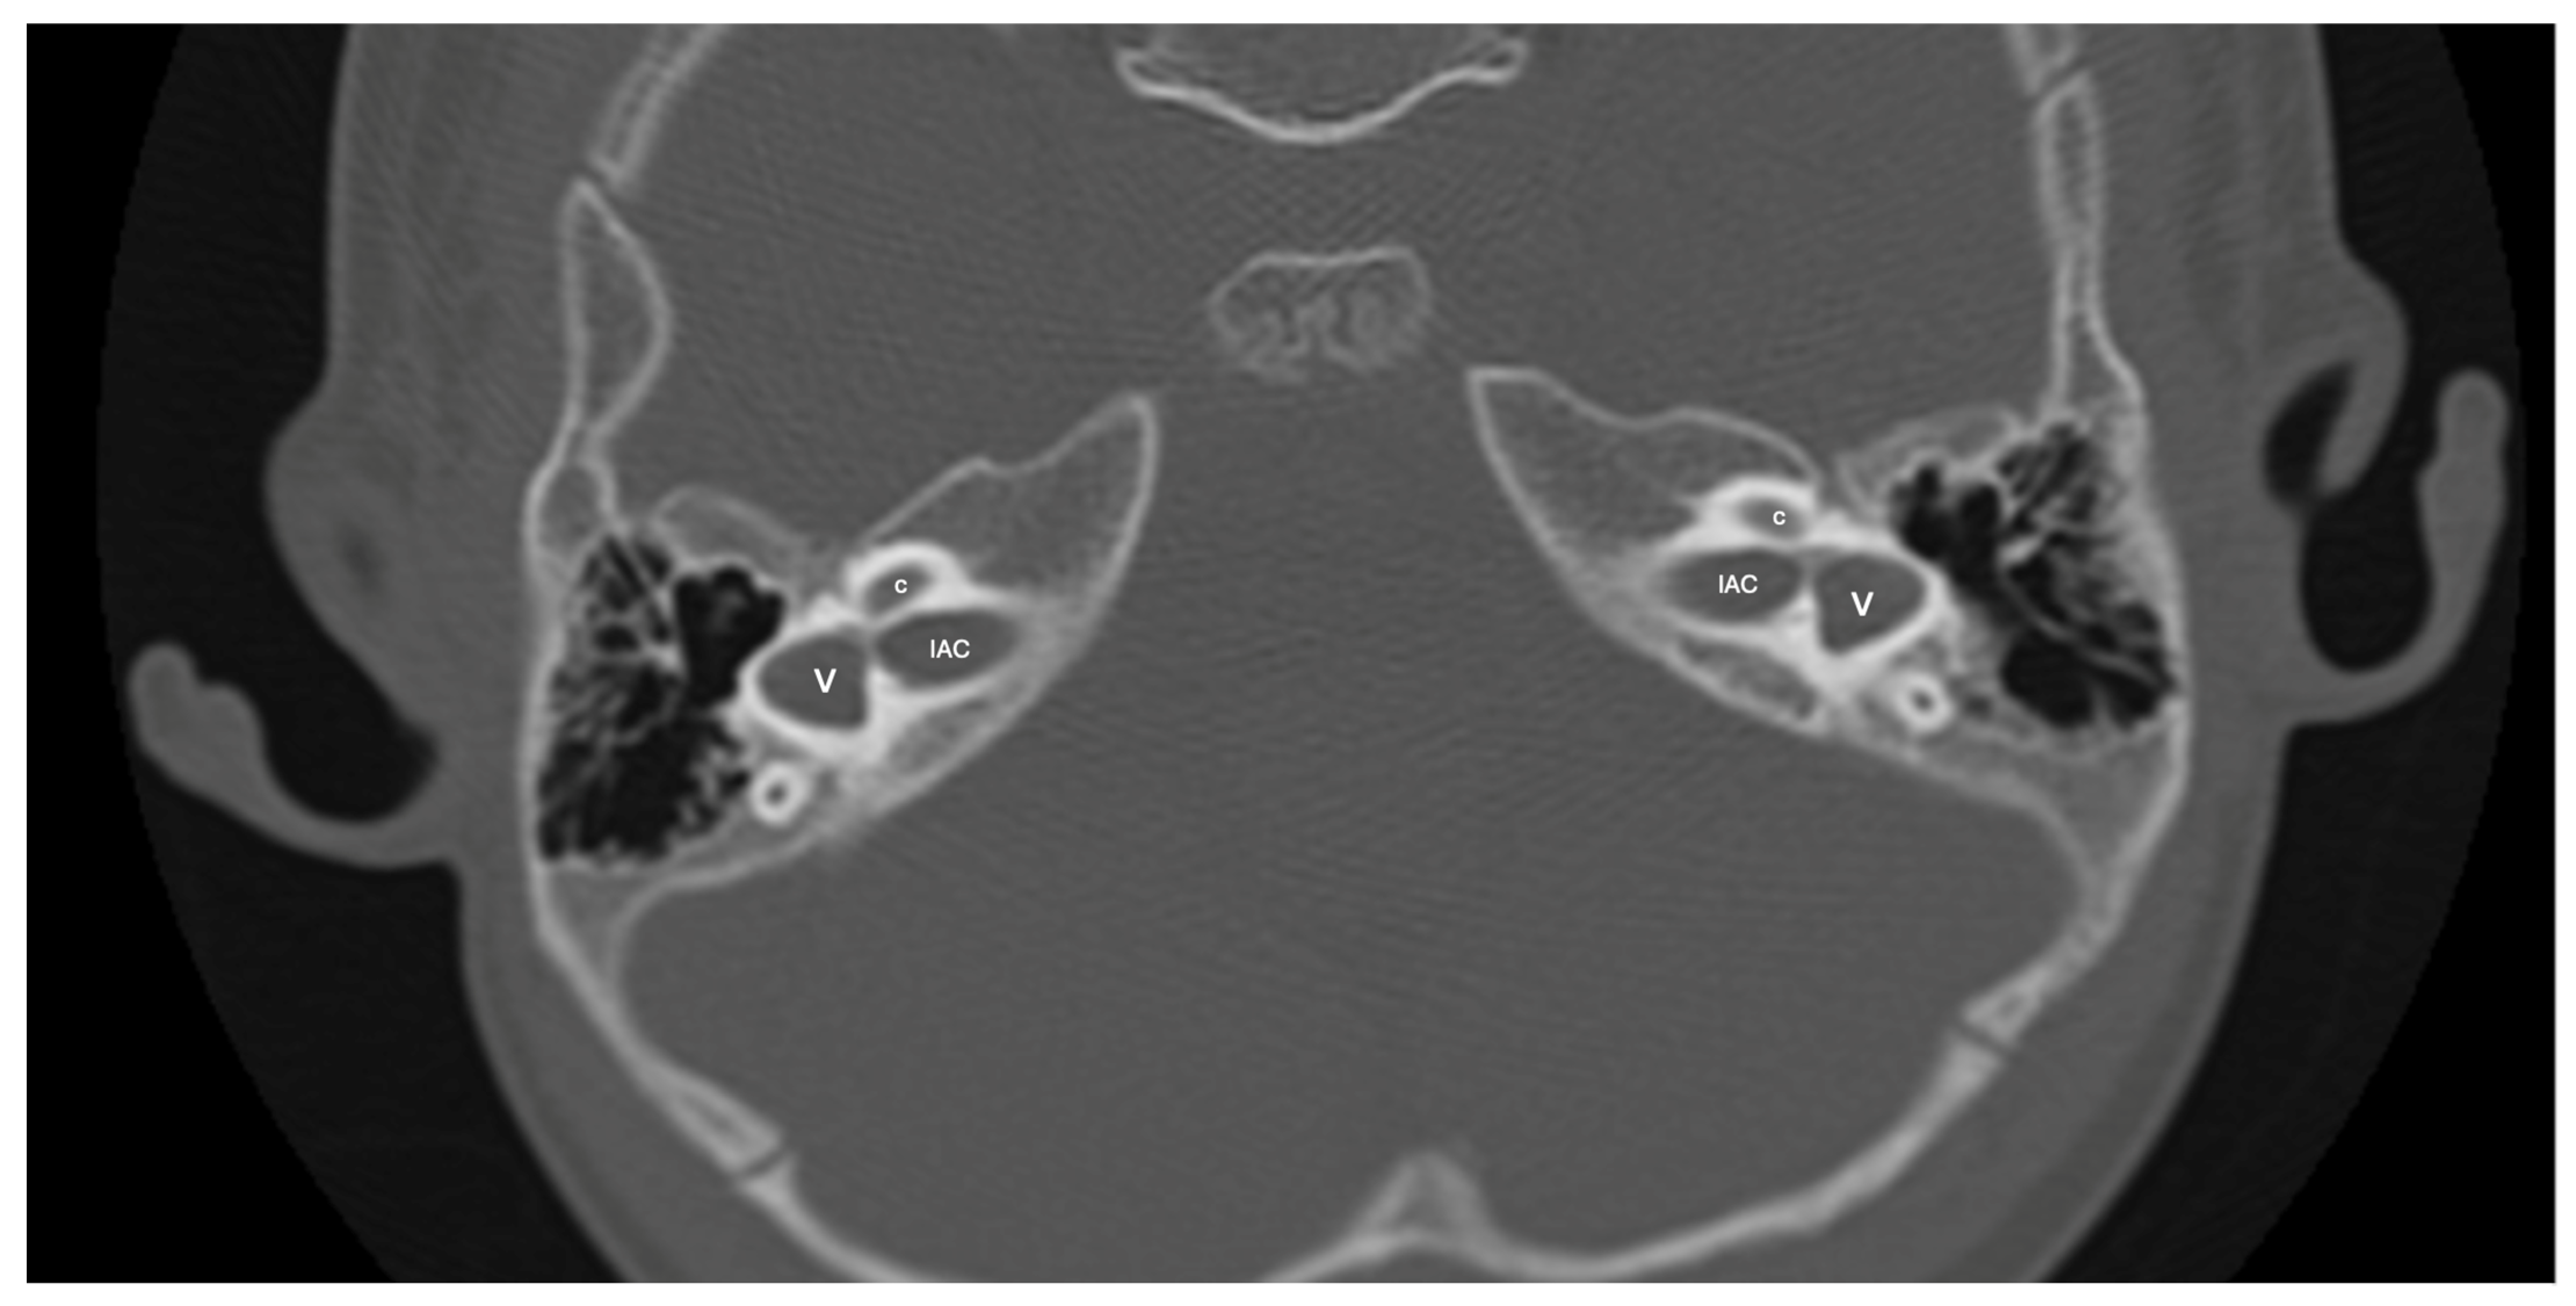

LCVD was detected in six ears of three patients, while isolated LSCCH was detected in six ears of three patients. No additional malformations were detected in these patients’ cochleae or other inner ear structures (Figure 5). Cochlear nerve anomalies were observed in 11 patients with a history of congenital SNHL. Among these, seven had bilateral hypoplasia, two had isolated right cochlear nerve hypoplasia, one had isolated left cochlear nerve aplasia, and one had left cochlear nerve hypoplasia while the right cochlear nerve could not be distinguished. Within this group, only one patient showed no cochlear anomaly.

Figure 5.

A case of bilateral lateral semicircular canal-vestibular dysplasia (LCVD). Both vestibules (v) are dilated and form a common cavity with the lateral semicircular canals (LSCC). The cochlea (c) can be normal (partially shown). IAC, internal acoustic canal.